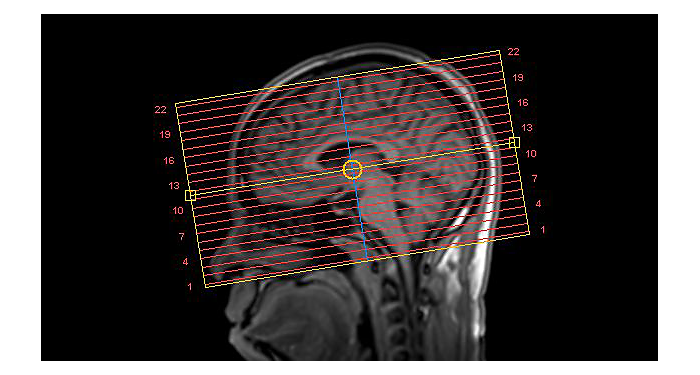

El 70% de los radiólogos consideran que las indicaciones neurológicas son un desafío, sobre todo debido a la falta de técnicas apropiadas de imagenología y visualización¹. Philips tiene como objetivo proporcionar la mejor claridad de diagnóstico posible y orientación terapéutica para todos los pacientes con trastornos neurológicos. Al aprovechar nuestra plataforma digital dStream, este año presentamos un conjunto de estrategias nuevas de imagenología y visualización. Esto puede ayudarlo a resolver preguntas sobre neurología complejas con mayor certeza, así como a desbloquear nuevos territorios neurológicos en aplicaciones neurofuncionales avanzadas. Este es un paso clave para aumentar el diagnóstico neurológico y, en última instancia, impactar más vidas con la RM. ¹ TMTG Market Survey 2016